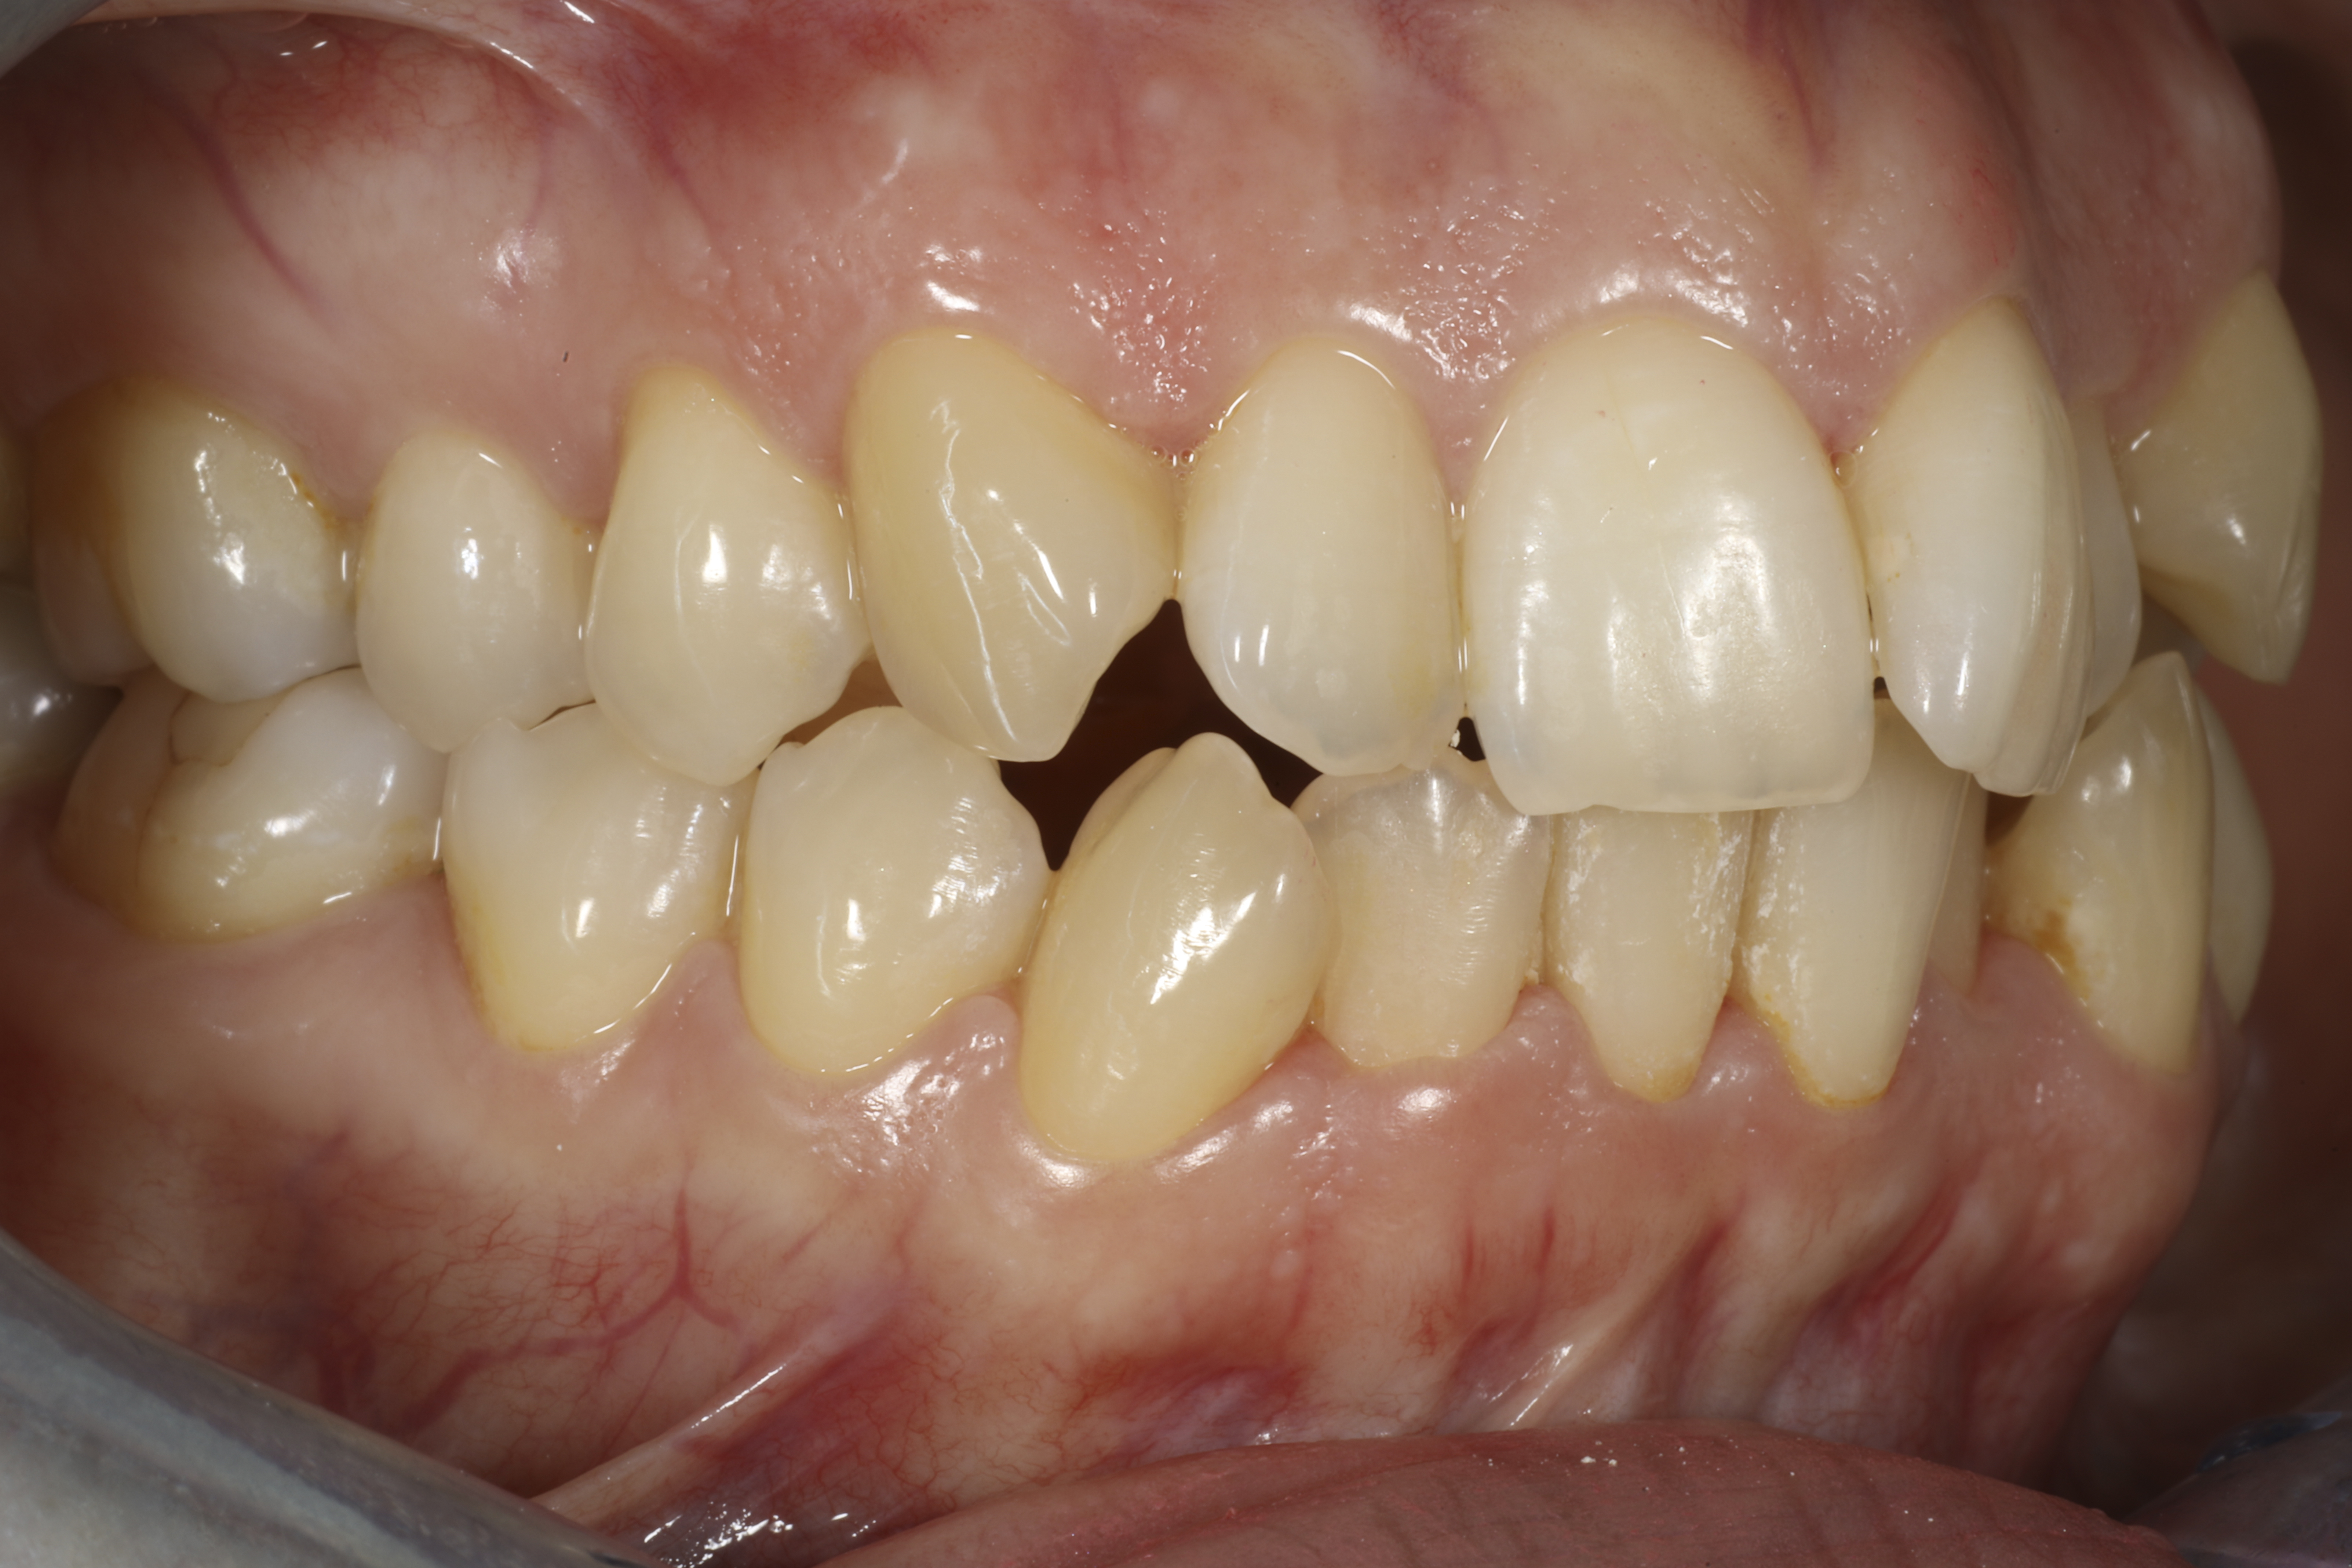

Alla suorittamiani hoitoja ja esimerkkejä siitä minkälaisia purentavirheitä voi korjata.

Mittaustavasta riippuen kahdella kolmasosalla aikuisista Suomalaisista on jonkiasteinen purentavirhe. Jos yläleuan hampaat ovat alahampaita edempänä, puhutaan mesiaalipurennasta ja toisinpäin distaalipurennasta. Näiden korjaamiseksi kalvoilla on pystyttävä liikuttamaan koko hammaskaaren hampaita suhteessa vastapuolen hampaisiin. Ilman linkkiä kalvojen välillä tämä ei tapahdu.